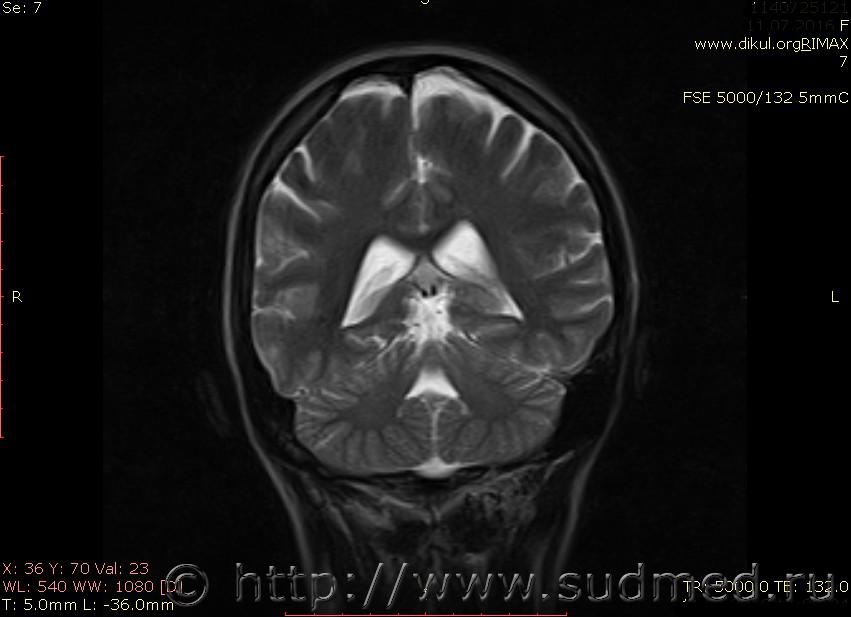

МРТ головного мозга показало: МР-данных за наличие очаговых изменений в веществе головного мозга на момент исследования не выявлено. МР-признаки нарушения соотношения в атланто-осевом суставе. Определяется ассиметрия положения зубовидного отростка С2 относительно боковых масс С1(справа 6,5; слева 4 мм.)

Сама по себе эта информация даёт основания подозревать вывих первого шейного позвонка, но однозначно не свидетельствует о наличии вывиха. Нужно смотреть на снимках наличие реакции со стороны мягких тканей, в т.ч. связочного аппарата, нужно анализировать особенности неврологической патологии, её динамику и проч.

Запрошен электронный вариант снимков из учреждения, где делалось МРТ. Т.к. с самого снимка делать копии не получается,очень мелкие кадры. Завтра попробую вставить в сообщение. (Но СМЭ снимок не смотрел, смотрел только мед.карту, в которой находилось описание МРТ).

Посмотрите пожалуйста снимки, надеюсь на них видны позвонки С1,С2?

Прошу прощения, попробую снова прикрепить файлы. Данные учреждения и пациента убраны.